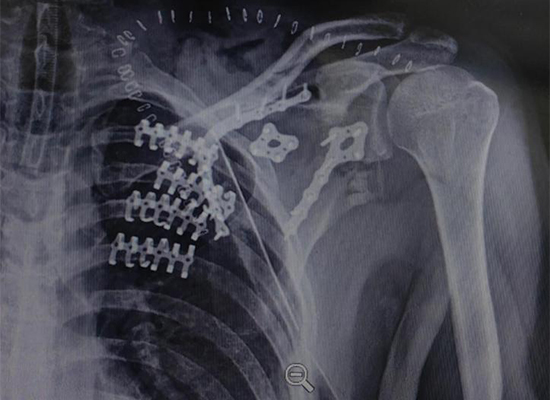

L'imagerie postopératoire a confirmé une fixation stable des segments costaux et une restauration de l'alignement thoracique. La cage thoracique a démontré une intégrité structurelle améliorée sans signe de déplacement de l'implant.

La construction de fixation a fourni une stabilité adéquate pour soutenir la fonction respiratoire postopératoire et les protocoles de rééducation.

Le résultat chirurgical a démontré un alignement anatomique restauré et une stabilité fonctionnelle de la paroi thoracique, confirmant l’efficacité de la stabilisation chirurgicale de la paroi thoracique dans ce cas de traumatisme. La vérification de l'imagerie et l'amélioration clinique ont indiqué une intervention réussie.

Le système de fixation costale se compose de plaques costales anatomiques et de vis de verrouillage correspondantes, permettant une fixation stable tout en conservant une conception à profil bas. Les plaques peuvent être profilées en peropératoire pour correspondre à l'anatomie individuelle des côtes, ce qui les rend adaptées à la fixation de la paroi thoracique antérieure, latérale et postérieure. Dans ce cas, le système a été appliqué pour stabiliser les segments costaux déplacés et rétablir la continuité de la cage thoracique.

De plus, un système de plaque de fixation de la clavicule a été appliqué pour traiter la fracture de la clavicule associée. La restauration de l'alignement et de la longueur des clavicules a contribué à la stabilité globale de la paroi thoracique et de la ceinture scapulaire, ce qui est particulièrement important dans les cas de traumatismes thoraciques combinés.